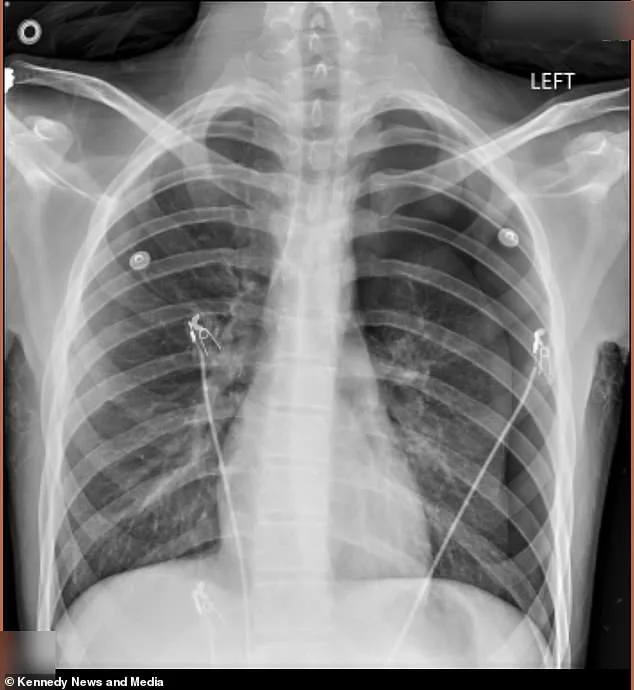

In September 2025, Dodge came home from school pale and in severe back pain. His mother rushed him to the emergency room, where a chest X-ray revealed that 50% of his left lung had collapsed, a condition known as pneumothorax. This occurs when air leaks into the chest cavity, creating pressure that pushes against the lung and causes it to collapse. Doctors had to surgically insert an 18-inch tube into his chest to remove the excess air and allow his lung to re-expand. The procedure was a medical emergency, and the family was left reeling from the sudden severity of the condition.

Despite the first incident, Dodge continued vaping in secret. That changed in January 2026, when he called his mother out of breath and in excruciating pain. He was rushed back to the ER, where doctors warned that his second lung collapse could have been fatal if not treated immediately. This time, the damage was more severe, prompting a more invasive surgery called pleurodesis. During the procedure, surgeons scraped the lining of his lung and stapled fluid-filled blisters, known as blebs, to the top of his lung to prevent further collapses. The surgery was described by Vann as 'horrible,' leaving her in a state of emotional and physical distress.